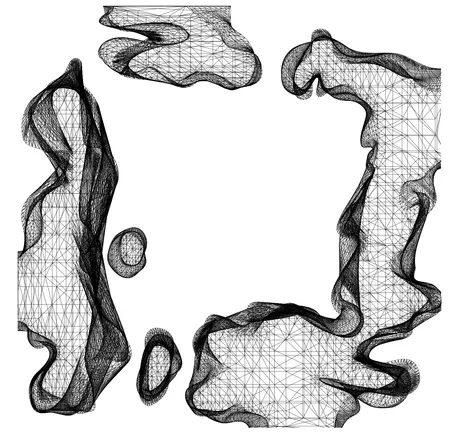

09 Volumetric Segmentation